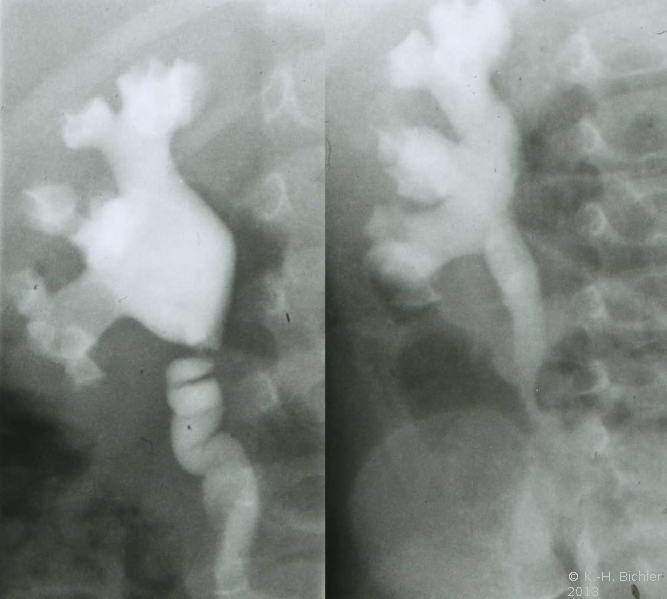

Ausgehend von einem Flankenschnitt (Intercostal) Freilegung des Nierenbeckens und Darstellung der Ureterabgangs (Engstellung, Taillierung), Resektion des Nierenbeckens und der Harnleiterengstelle. Naht des spatulierten Harnleiters an das resizierte und mit Naht verschlossene Nierenbecken (Abbildung HG1).

Als Beispiel die Ureterabgangsstenose bei multiplen Nierenbeckenkelchsteinen eines 2 Jahre alten Jungen (Abbildung HG2).